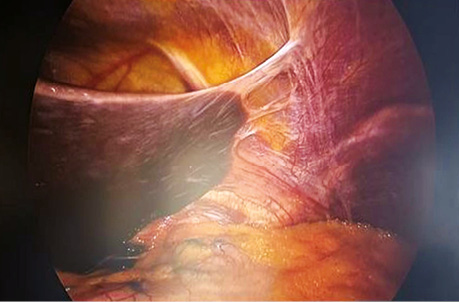

Перед початком лікування проведено діагностичну лапароскопію та виключено наявність метастатичного ураження в черевній порожнині (рис. 2).

Рис. 2. Інтраопераційне фото черевної порожнини при діагностичній лапароскопії